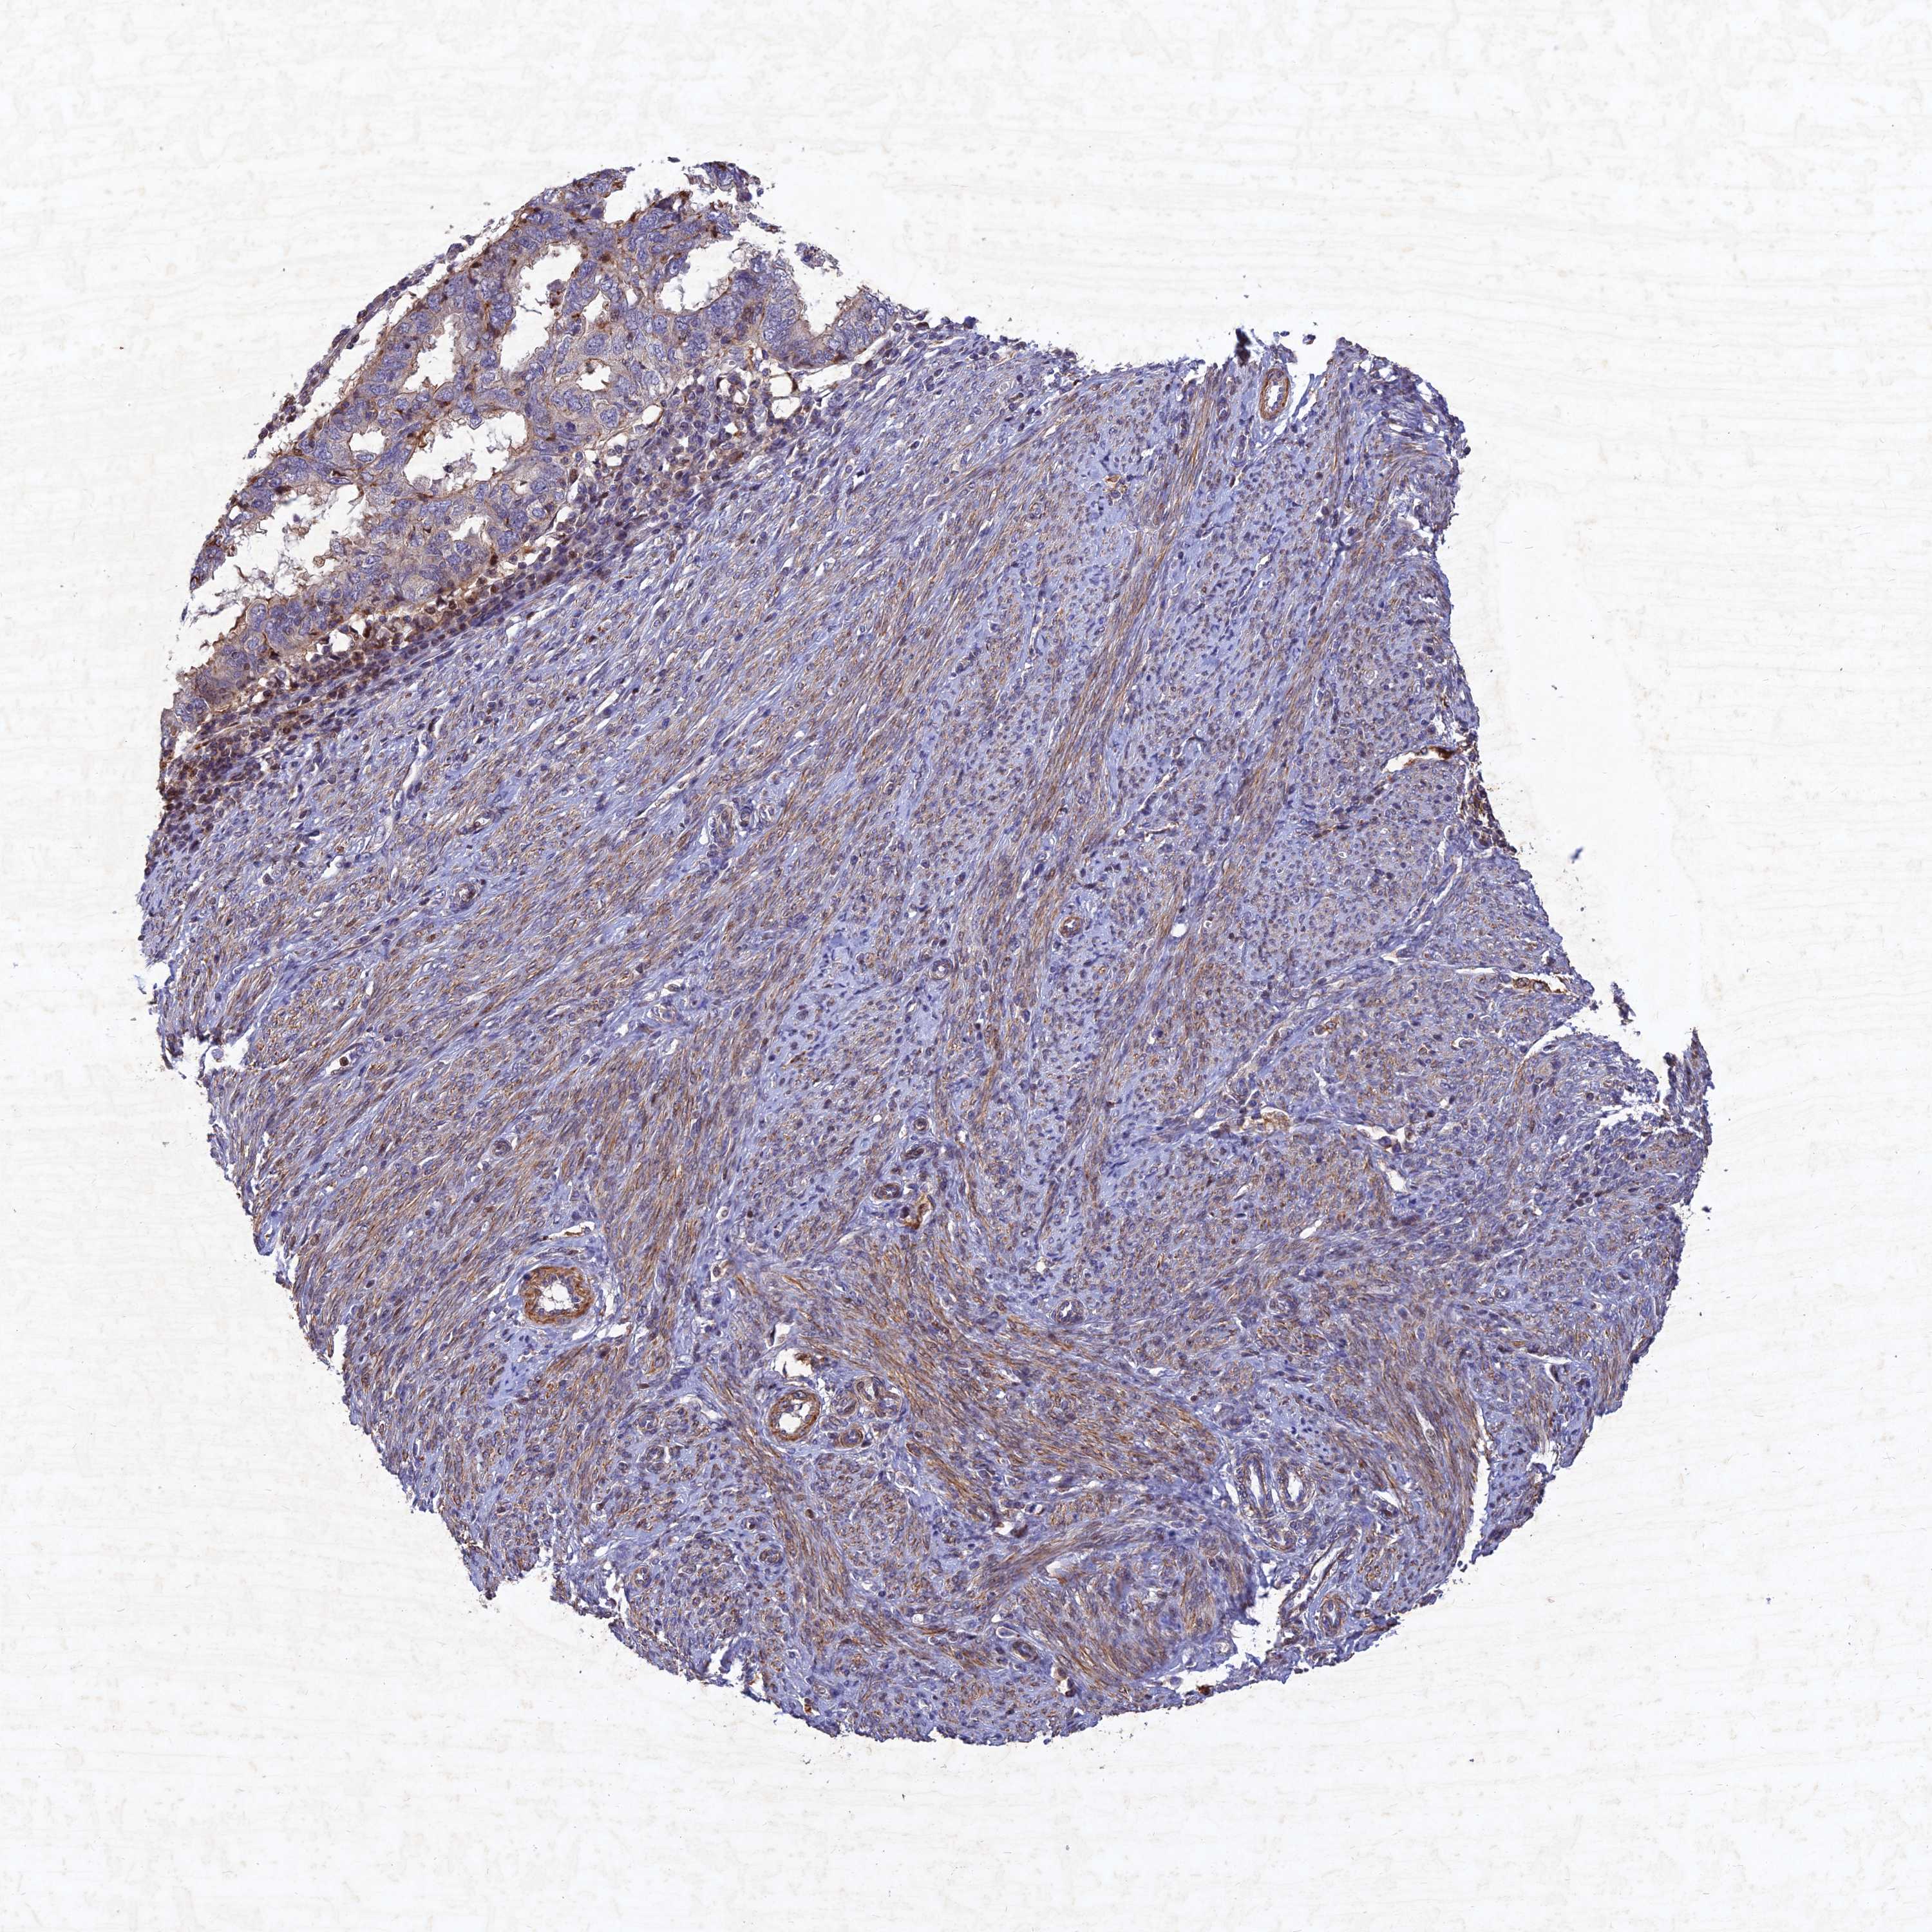

ENDOMETRIAL CANCER - Protein expressioni

A mouse-over function shows sample information and annotation data. Click on an image to view it in a full screen mode. Samples can be filtered based on level of antibody staining by selecting one or several of the following categories: high, medium, low and not detected. The assay and annotation is described here.

Note that samples used for immunohistochemistry by the Human Protein Atlas do not correspond to samples in the TCGA dataset.

Antibody stainingi

Antibody staining in the annotated cell types in the current human tissue is reported as not detected, low, medium, or high, based on conventional immunohistochemistry profiling in selected tissues. This score is based on the combination of the staining intensity and fraction of stained cells.

Each image is clickable and will lead to virtual microscopy that enables deeper exploration of all samples and also displays staining intensity scores, fraction scores and subcellular localization as well as patient and tissue information for each sample.

Antibody HPA039708

Antibody HPA040038

Staining

High

Medium

Low

Not detected

Intensity

Strong

Moderate

Weak

Negative

Quantity

>75%

75%-25%

<25%

None

Location

Nuclear

Cytoplasmic/membranous

Cytoplasmic/membranous,nuclear

Adenocarcinoma, NOS

Adenocarcinoma, metastatic, NOS